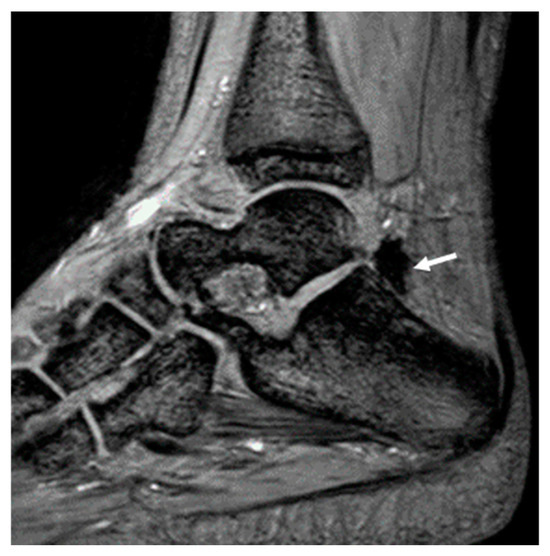

- Akyuz, B.; Polat, A.V.; Ozturk, M.; Aslan, K.; Tomak, L.; Selcuk, M.B. Contribution of 3-T susceptibility-weighted MRI to detection of intraarticular hemosiderin accumulation in patients with hemophilia. AJR 2018, 210, 1141–1147. [Google Scholar] [CrossRef]

- Zhang, L.; Wei, S.; Li, J.; Wang, P.; Ge, Y. Value of 3.0T MRI T2 mapping combined with SWI for the assessment of early lesions in hemophilic arthropathy. Hematology 2022, 27, 1263–1271. [Google Scholar] [CrossRef] [PubMed]

- Prasetyo, M.; Mongan, A.E.; Chozie, N.A.; Prihartono, J.; Setiawan, S.I. Hemosiderin deposition evaluation in hemophilic ankle joints: Association between US finding and gradient-recalled echo MR imaging sequence. Insights Imaging 2021, 12, 107. [Google Scholar] [CrossRef]